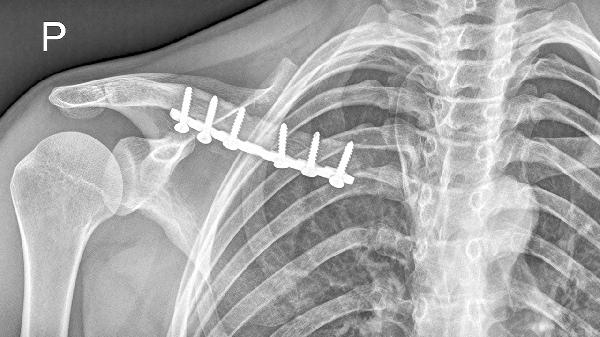

1、外伤:如果您近期曾经遭受过撞击或挤压,可能导致右锁骨区域的软组织损伤和肿胀,从而引发疼痛。面对这种情况,您可以在受伤后的24小时内进行冰敷,以减少肿胀和缓解疼痛。24小时后,可以通过热敷促进血液循环,加速恢复。遵医嘱服用止痛消炎药物,如布洛芬缓释胶囊或双氯芬酸钠缓释片,也能帮助缓解不适。